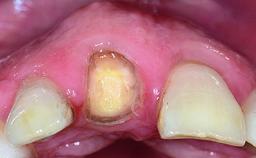

Replacement of a Failing Restored Upper Right Central Incisor, Ridge Preservation and Early Placement of an RC Bone Level Implant

A 23-year-old female, healthy and non-smoking patient had had tooth 11 temporarily restored following a trauma in adolescence. As the patient’s growth had since come to an end and the crown had fractured, she requested an implant-supported restoration of tooth 11. Moreover, the contralateral tooth 21 presented an old composite restoration at the mesial incisal edge. The periodontal tissues were healthy with periodontal probing depth values below 3 mm, but some inflammation was observed around the semi-submerged root of tooth 11.